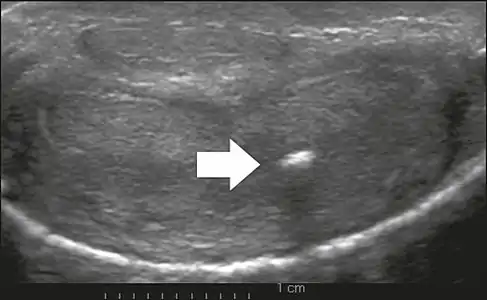

- Figure 6: Transverse ultrasound of the penis, in a ventral view, in the middle portion of the penis. Note the echoic image with posterior acoustic shadowing, corresponding to calcification (arrow), in the left corpus cavernosum.[1]